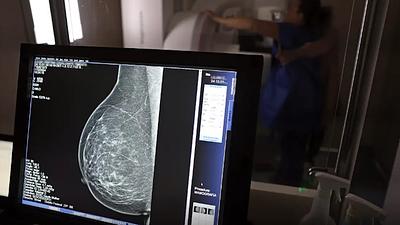

Escassez de mamógrafos dificulta prevenção do câncer de mama

O Brasil tem uma cobertura muito baixa de mamografias: 24%. O ideal recomendado pela Organização Mundial da Saúde é de 70%.